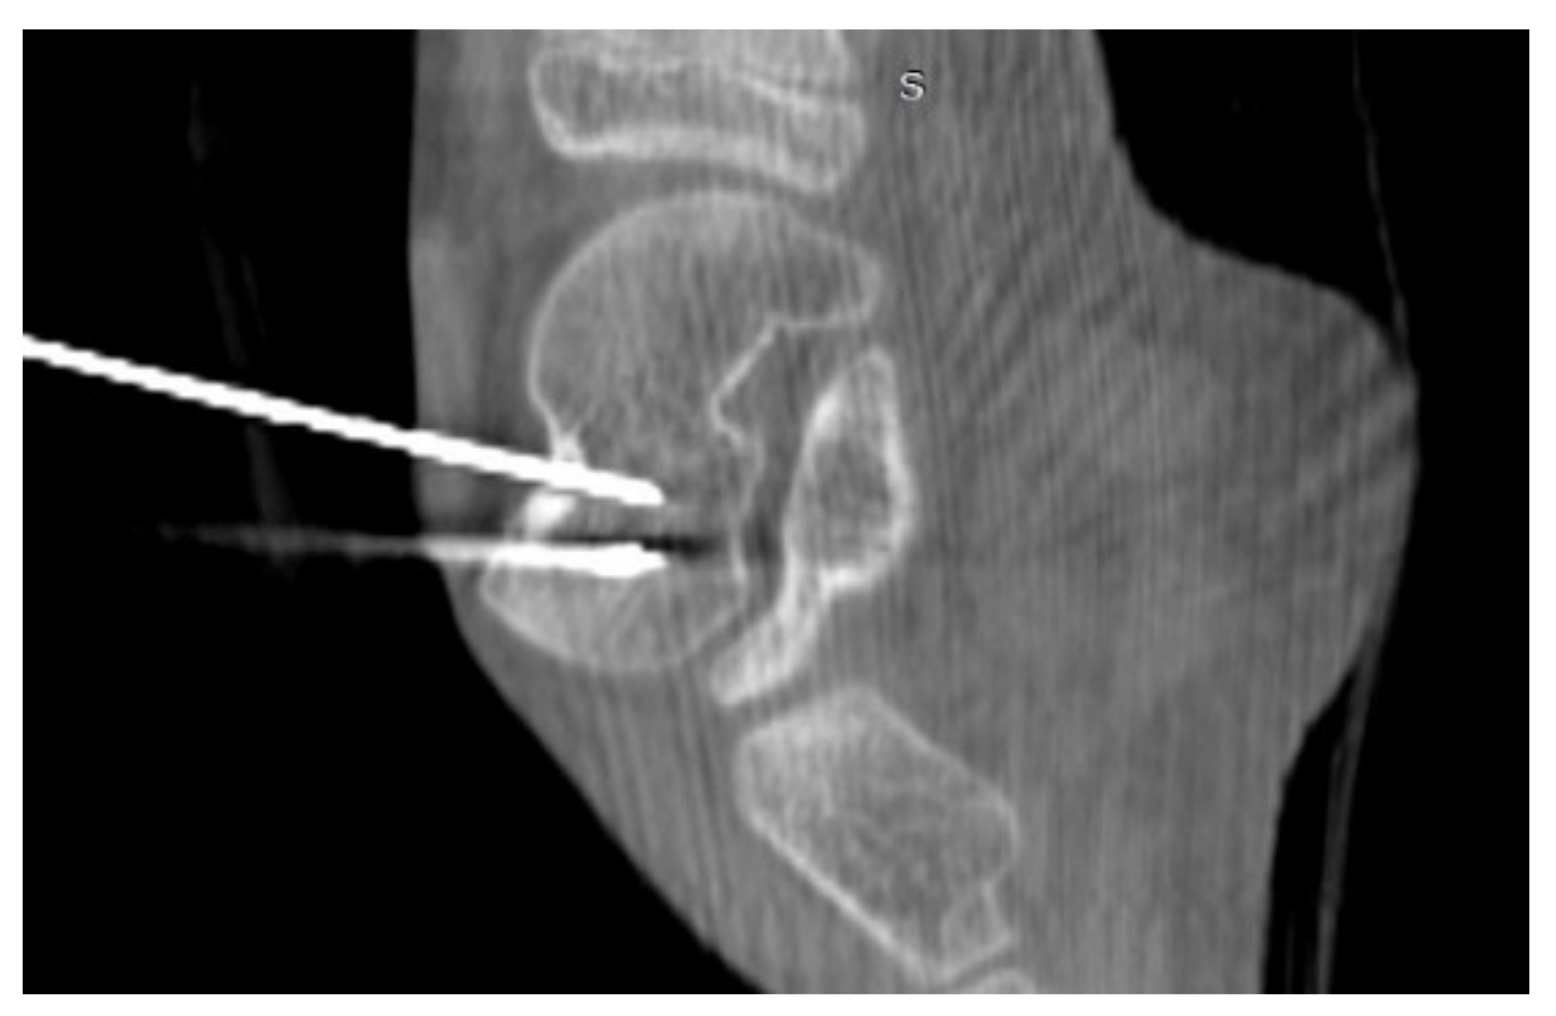

3.1. Case 1: OO Masking as Femoroacetabular Impingement (FAI)